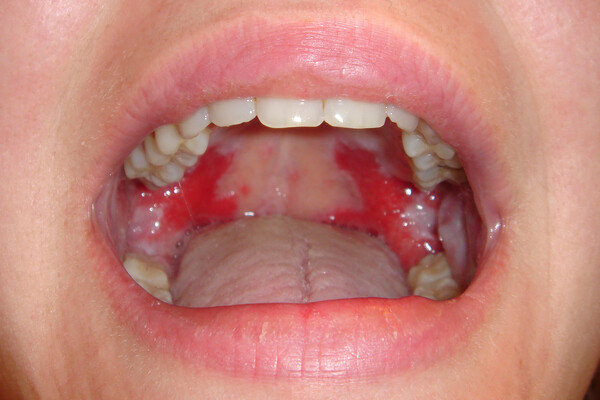

What Causes Red Spots On The Roof Of Your Mouth?

Red spots on the roof of your mouth can be caused by a variety of different reasons. Some are just a minor inconvenience, while others could be a sign of a more serious health issue that may require further investigation. Here are some common possibilities:

Coxsackievirus

The virus behind hand, foot and mouth disease, coxsackievirus can cause painful blisters and red spots on the roof of the mouth, as well as on the hands and feet. It is most common in children under five years of age, but does occur in people of all ages. Treatment options include over-the-counter medications for fever and pain, as well as special medicated mouthwashes to help alleviate the discomfort associated with the oral sores.